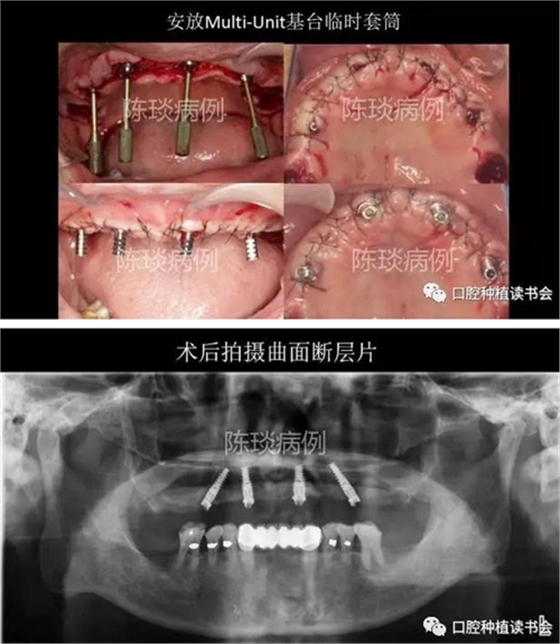

5,種植外科流程:

(1)數(shù)字化導(dǎo)板引導(dǎo)下完成種植體植入。

(2) 種植體植入術(shù)后制作臨時(shí)修復(fù)體即刻修復(fù)。